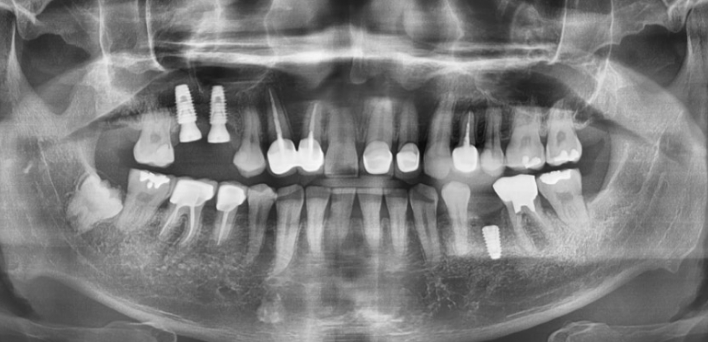

더서울치과의원은 개인의 얼굴과 가장 잘 어울리는 치아의 형태와 색상을 분석하고,

분석한 데이터를 기반으로 맞춤형 보철을 진행합니다.

더서울치과의원은 정확한 안모 분석을 통한 프로파일 예측 치료로 심미성은 물론 치아 본연의 기능 회복까지 가능하도록

안면 근육과 기능, 치아 형태, 비율, 크기, 교합, 색감 등 전반적인 비율을 맞추어 본인에게 잘 맞는 치아의 형태로 복원합니다.

치아복구 + 치아성형 2가지의 장점을 합쳐

개개인 손상 정도에 따른 맞춤형 보철을 제작합니다.